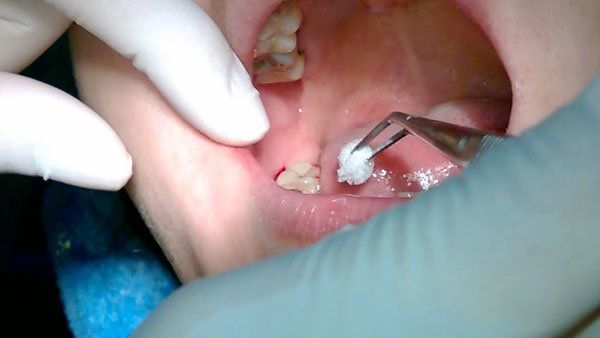

4. Lưu ý quan trọng sau khi nhổ răng khôn

Để vết thương nhổ răng nhanh lành và tránh viêm nhiễm, bạn cần lưu ý và tuân thủ những hướng dẫn sau:

• Cắn gạc 30 – 45 phút để cầm máu sau khi nhổ răng.

• Không chạm tay, đẩy lưỡi hay vật cứng vào vùng nhổ.

• Hạn chế đánh răng và không súc miệng quá mạnh trong 24 giờ đầu.

• Chườm lạnh để giảm sưng.

• Ăn thức ăn mềm, nguội, tránh đồ quá nóng hoặc cứng.

Nếu xuất hiện tình trạng đau kéo dài, sốt, chảy máu nhiều không cầm, hãy đến ngay Nha Khoa để được kiểm tra ngay.